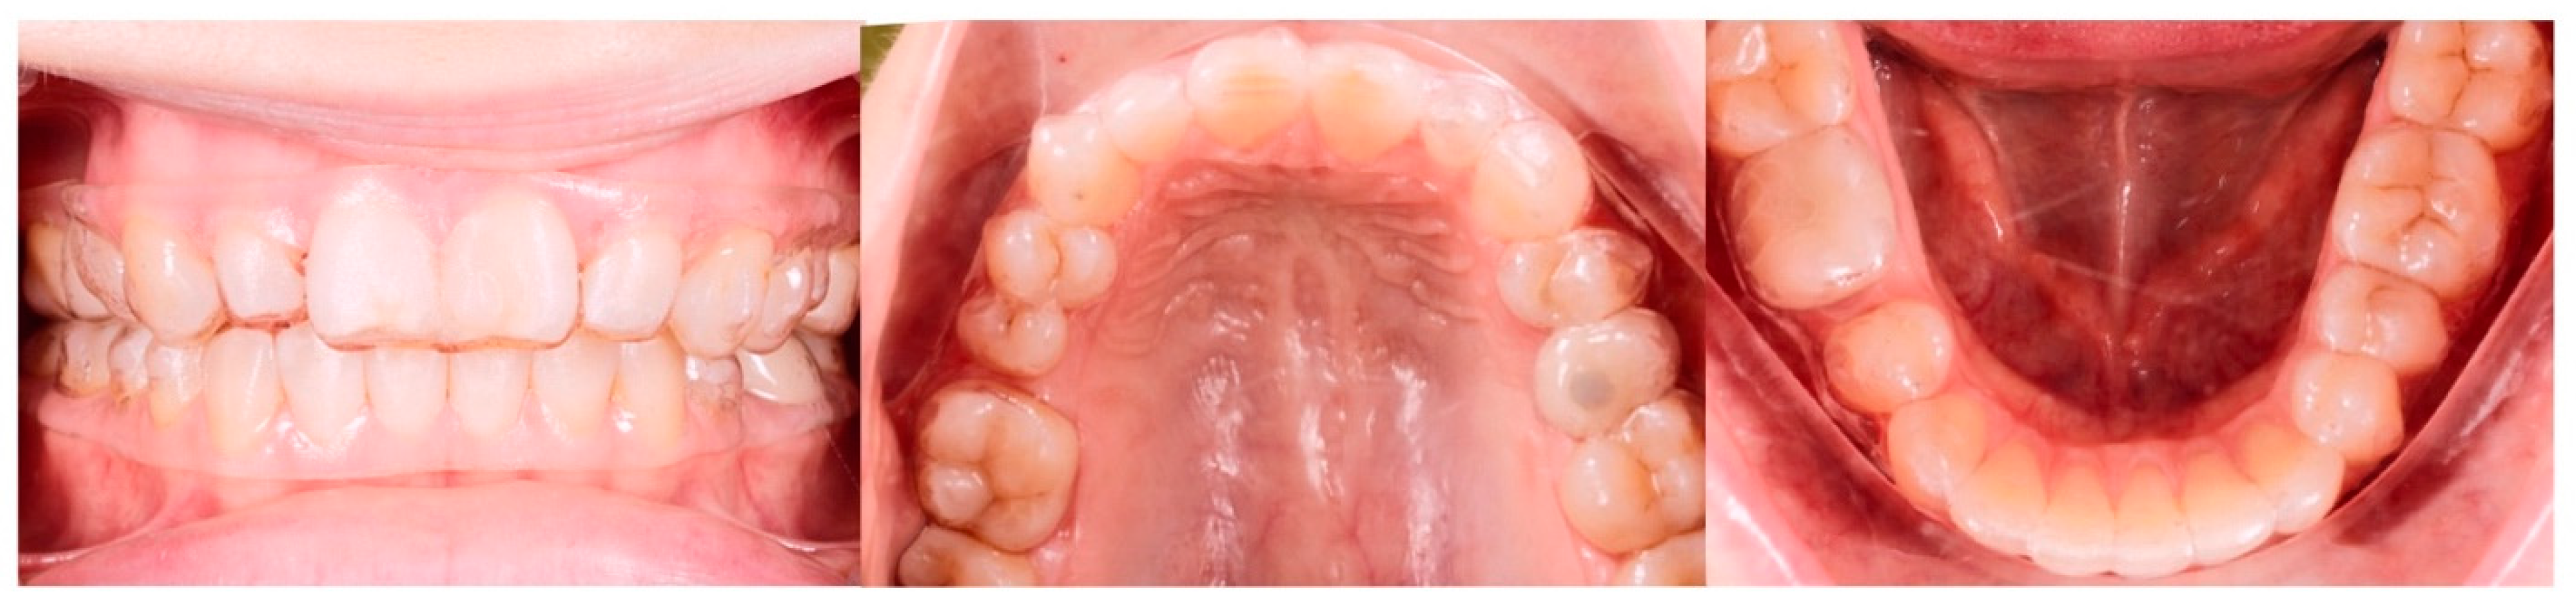

2.4. Pre-Restorative Records